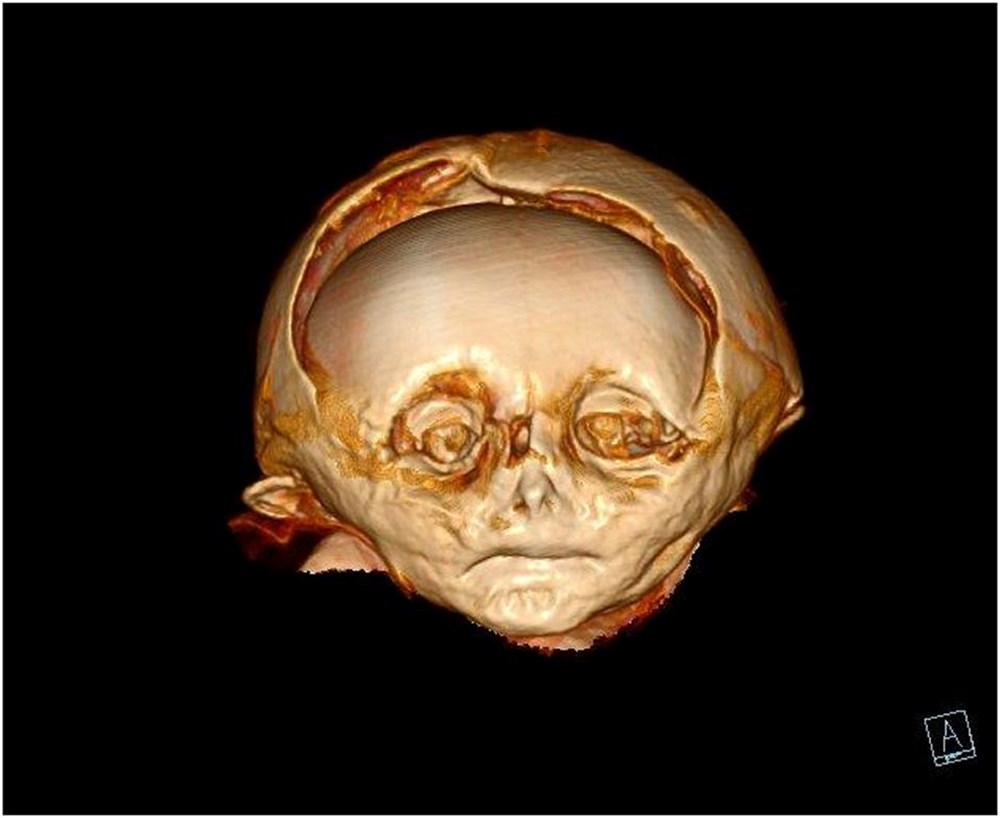

Alman bilim adamları, 17. yüzyıldan kalma bir Avusturya mezarlığında mumyalanmış bir çocuğun cesedi üzerinde ‘sanal otopsi’ gerçekleştirdi.

Kafatası deforme olan ve biraz küçük olan tahta bir tabuta gömülen küçük çocuğun vücudu hem obez hem de yetersiz beslenmiş gibi görünüyordu. Frontiers in Medicine’de yayınlanan çalışmada araştırmacılar, bulguların tarihi Avusturya aristokrat toplumuna ender bir bakış açısı sağlayabileceğini söyledi.

Bilim adamları, CT taramasını kullanarak, mahzen koşullarında doğal olarak mumyalanan mumya üzerinde ‘sanal otopsi’ yapabildiler. İyi korunmuş yumuşak doku, çocuğun bir erkek olduğunu, yaşına göre fazla kilolu olduğunu gösterdi ve radyokarbon tarihlemesi ise MS 1550 ile 1635 arasında bir ölüm tarihini gösterdi.